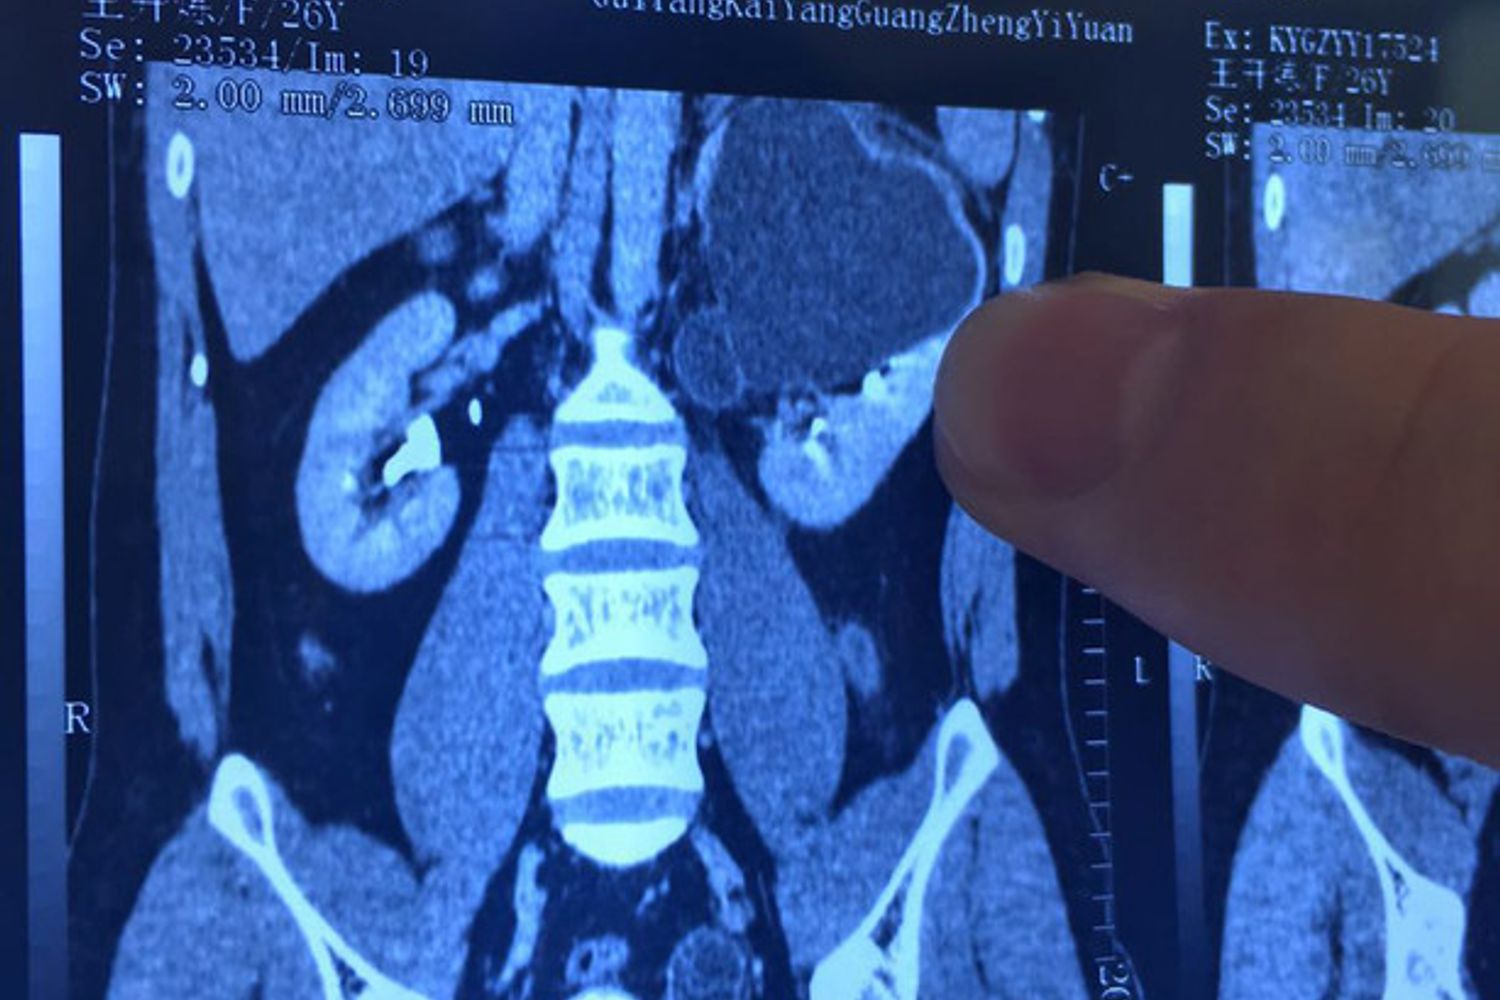

CREDITLI JIAN / IMAGINECHINA - La radiografia di un rene